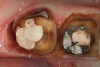

Figure 11  An occlusal view of tooth No. 5 after preparation has been made for a full-coverage restoration.

Figure 11

Figure 12  The needle electrosurgery electrode was used to "trough" around the lingual of the preparation to expose the preparation margin.

Figure 12

Figure 13  Troughing was completed on the proximal and lingual aspects of the preparation to aid in retraction cord placement prior to making the master impression. The marginal gingiva on the facial aspect was too thin to perform troughing without risking vertical loss of tissue.

Figure 13